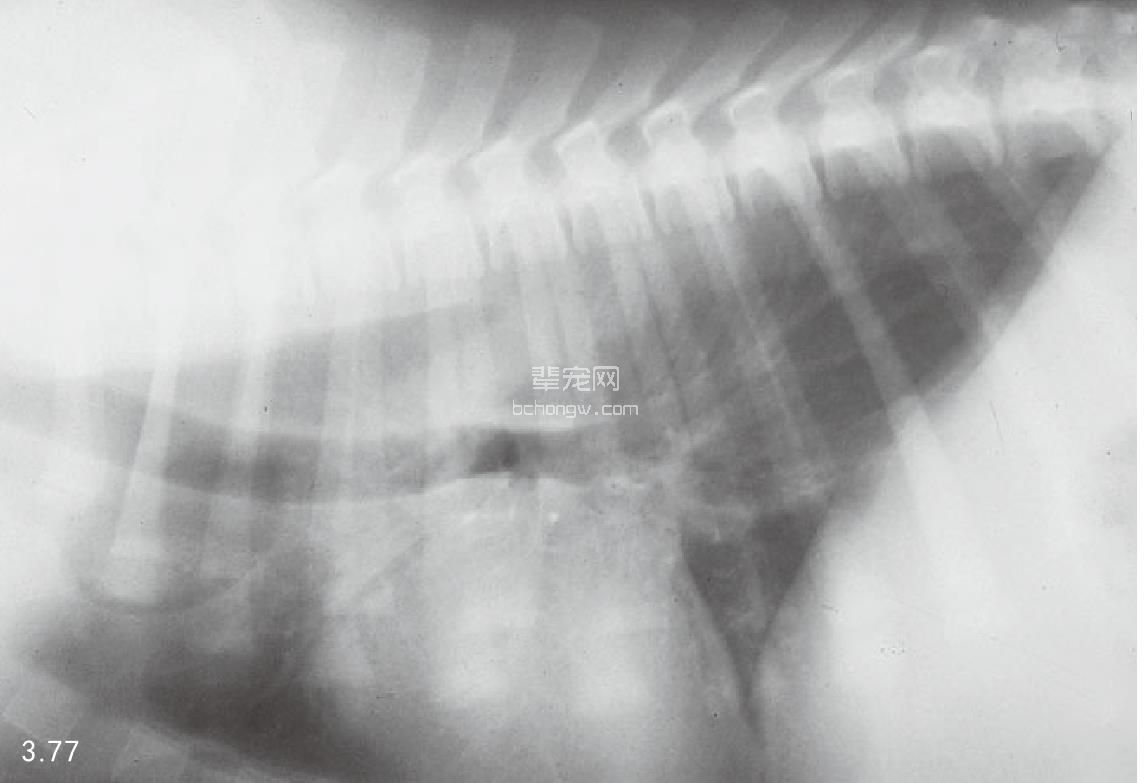

诊断 通过病史和胸腔常规X线片可以诊断 (图3.77~图3.80),但如果需要确定特殊的病 因,则需要进行额外的试验(表3.7)。如果不能 确诊可以做食管X线片和食管镜试验,但通常没有 这个必要(图3.81和图3.82)。德国牧羊犬、大丹 犬、爱尔兰赛特犬、小型雪纳瑞犬和硬毛 易患 先天性巨食管症。犬胃扩张-扭转综合征时,也 可能暂时性继发巨食管症。

图3.77 16周龄德国牧羊犬具有“玩耍时发生呕吐”史,胸腔X线检查发现为巨食管症。